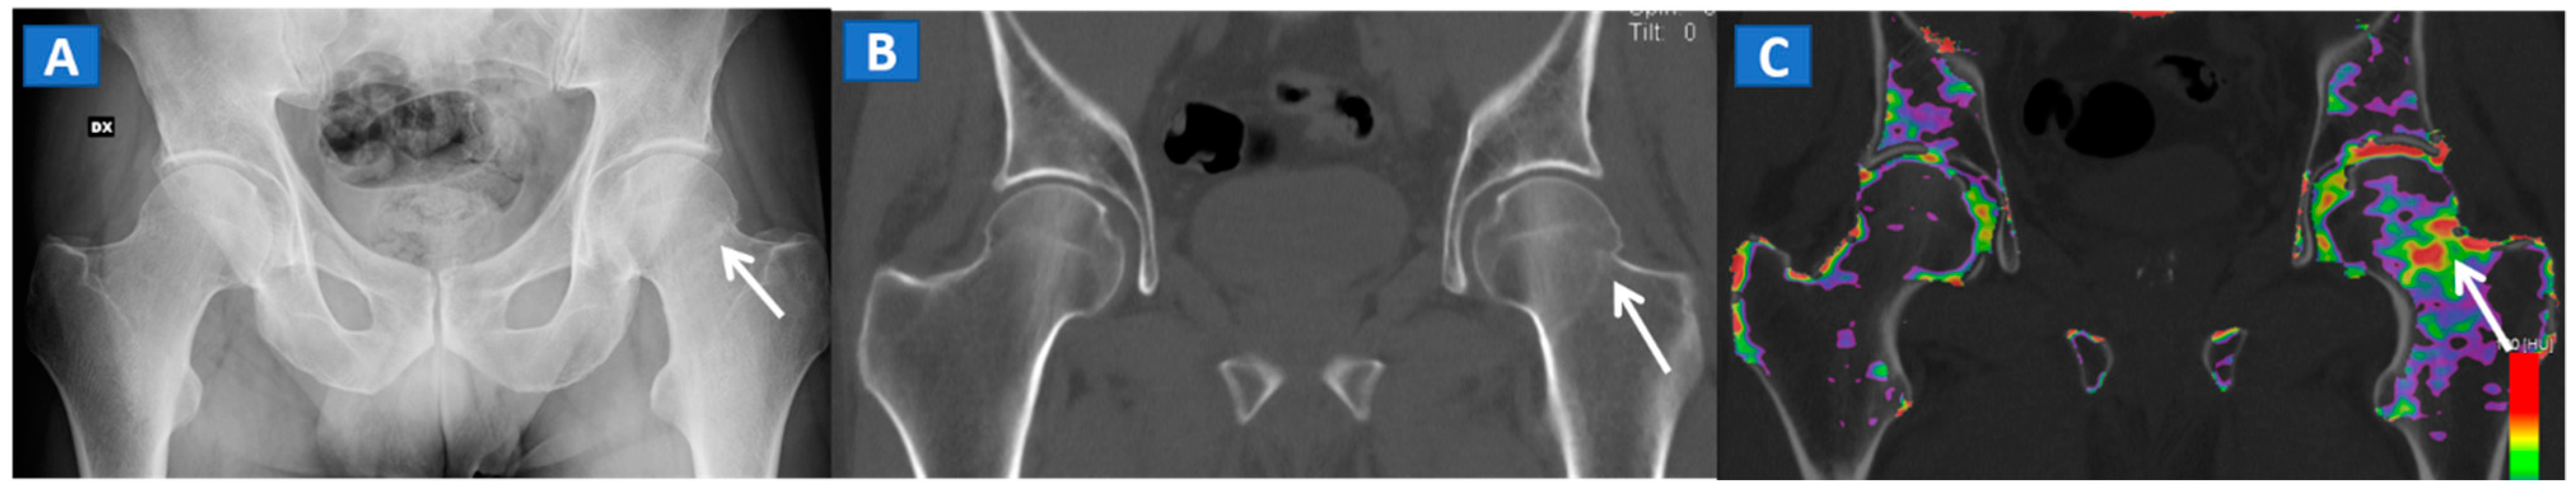

Figure 3.

A 51-year-old male with a non-displaced left cervical fracture. On the coronal standard radiograph (A), a meshed fracture is suspected on the left side because of an apparent cortical irregularity (arrow). On the corresponding standard reconstructed 1 mm CT image (B), a subtle cortical irregularity is confirmed (arrow). On the corresponding DECT reconstructed coronal 1 mm image (C), severe BME clearly delineates the fracture line (arrow), which is surrounded by a mild oedema halo involving the trochanteric region.

5. The Lower Limb: Hip, Knee, Ankle, and Foot

DECT can also accurately depict BME in traumatic hip injuries [2]. When evaluating pelvic bones, multiple non-displaced but clinically relevant fractures frequently arise in clinical practice, for instance, untreated cervical hip fractures, which risk future displacement (Figure 3). In such cases, DECT can increase the diagnostic accuracy and reduce the reading time, allowing the radiologist to identify and focus on oedematous areas, which usually correspond to the facture line. DECT also helps in depicting multiple fractures (Figure 4), avoiding the risk of satisfaction of search errors.